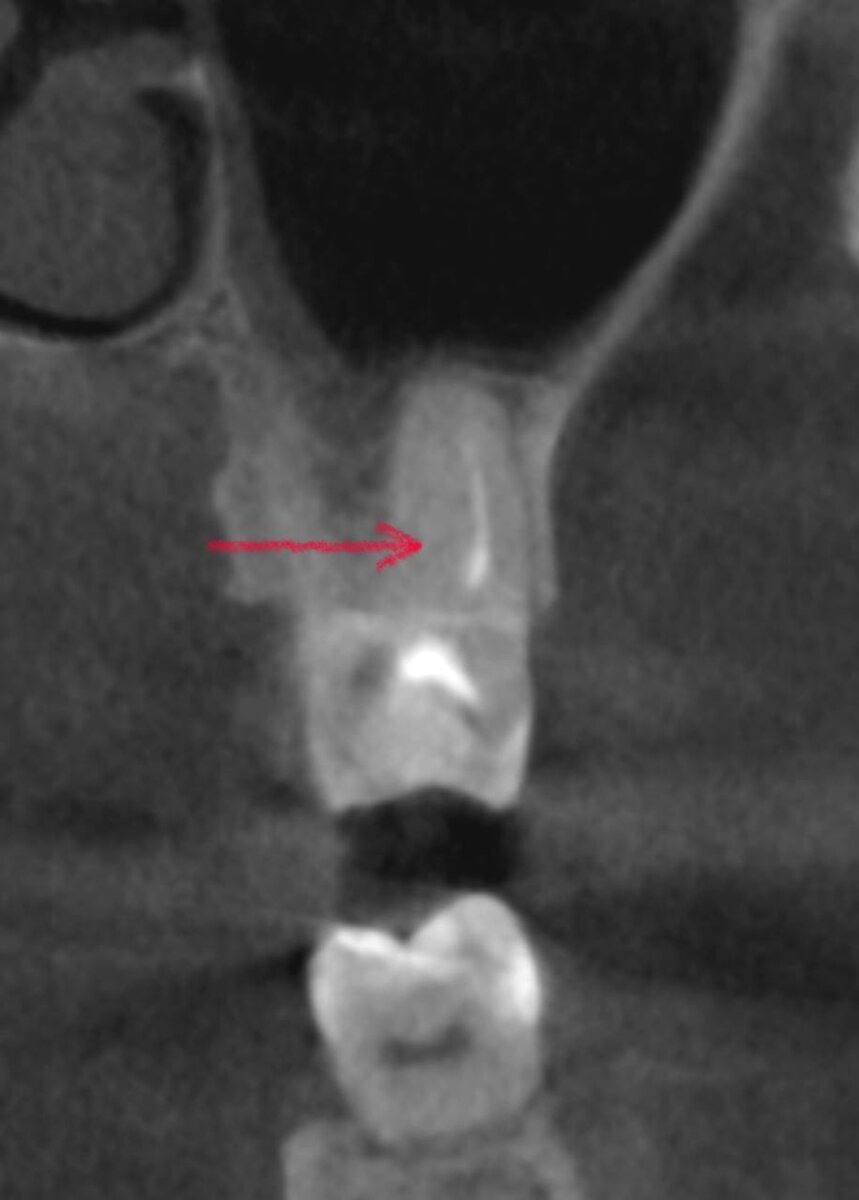

MB2 - о, это не просто узкий мелкий канал. Это канал с изгибом! Почти всегда - резким, дерзким, в самом начале, там, где инструмент только начинает свой путь.

Именно этот изгиб делает MB2 одним из самых опасных каналов в эндодонтии.

Виден изгиб, ведущий в МВ2:

Изгиб, ведущий в MB2 канал

MB1 и MB2 идут отдельно, каждый своим ходом. На снимке видим длинные каналы, очень длинные корни. Семёрка стоит далеко, работа велась с коффердамом (обязательно) - выполнить прицельный рентгенологический снимок так, чтобы все верхушки были видны на одном кадре, весма непросто. Два снимка добавляю, на одном хорошо видны ходы MB1 и MB2, на другом - верхушки. Вместе они дают полную картину.